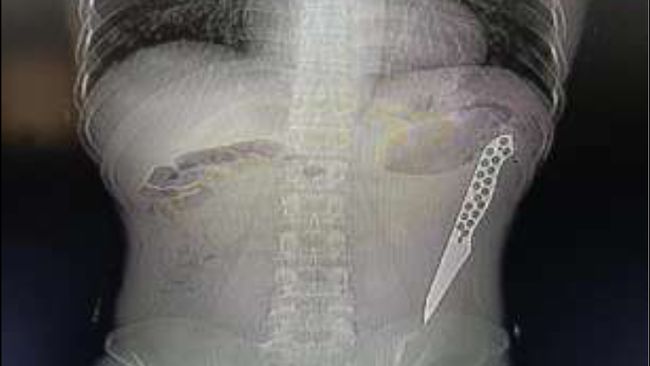

Foto: International Surgery Journal

CT scan memperlihatkan pisau berada di bagian usus besar pada area pinggang kiri. Tim dokter kemudian melakukan operasi laparotomi darurat untuk mengangkat benda asing tersebut. Pisau sepanjang sekitar 17,78 cm berhasil dikeluarkan tanpa adanya tanda peradangan pada selaput usus. Usus ditutup secara primer, dan kondisi pasien membaik setelah operasi.